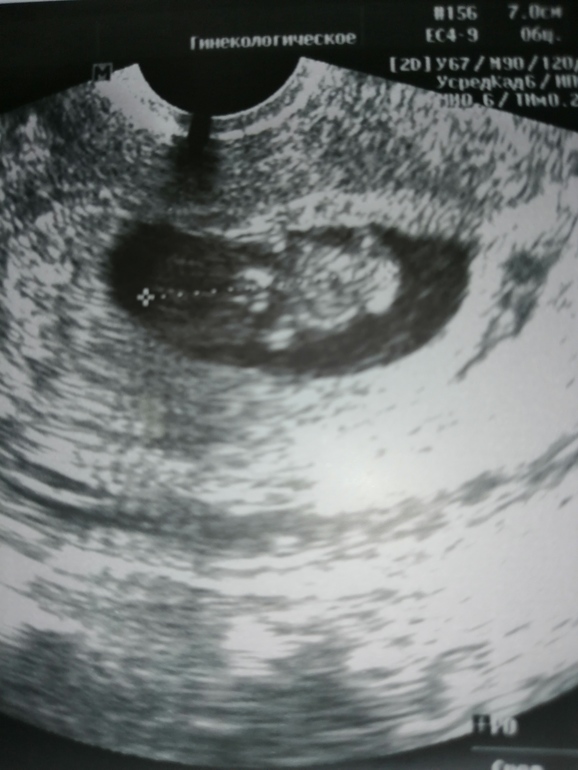

9 недель 4 дня или кретический период пройден🤔

УЗИ, КТГ, доплерСегодня опять решила сходить на узи, т.к для меня предыдущие дни были кретический периодом в прошлом... И мы вроде его прошли🙏по УЗИ поставили 10 неделек, малышу походу не понравилась процедура-весь крутился, постоянно шевелил ножками и ручками😊свд-36мм,ктр-27мм,с/б168-174(ритмичное) ,хорион-9,4мм(по задней стенке) жм-5,5мм

Самое интересное что 17 числа мне ктр намерили 23,4мм(другая клиника) не мог же мой ребёнок почти за неделю так мало вырасти, выходит кто то не правильно намерил🤷♀️

Я посмотрела свое узи в 7+5 в той же клинике, что и сегодня там ктр-15мм,а сегодня 27мм посчитала вроде норм